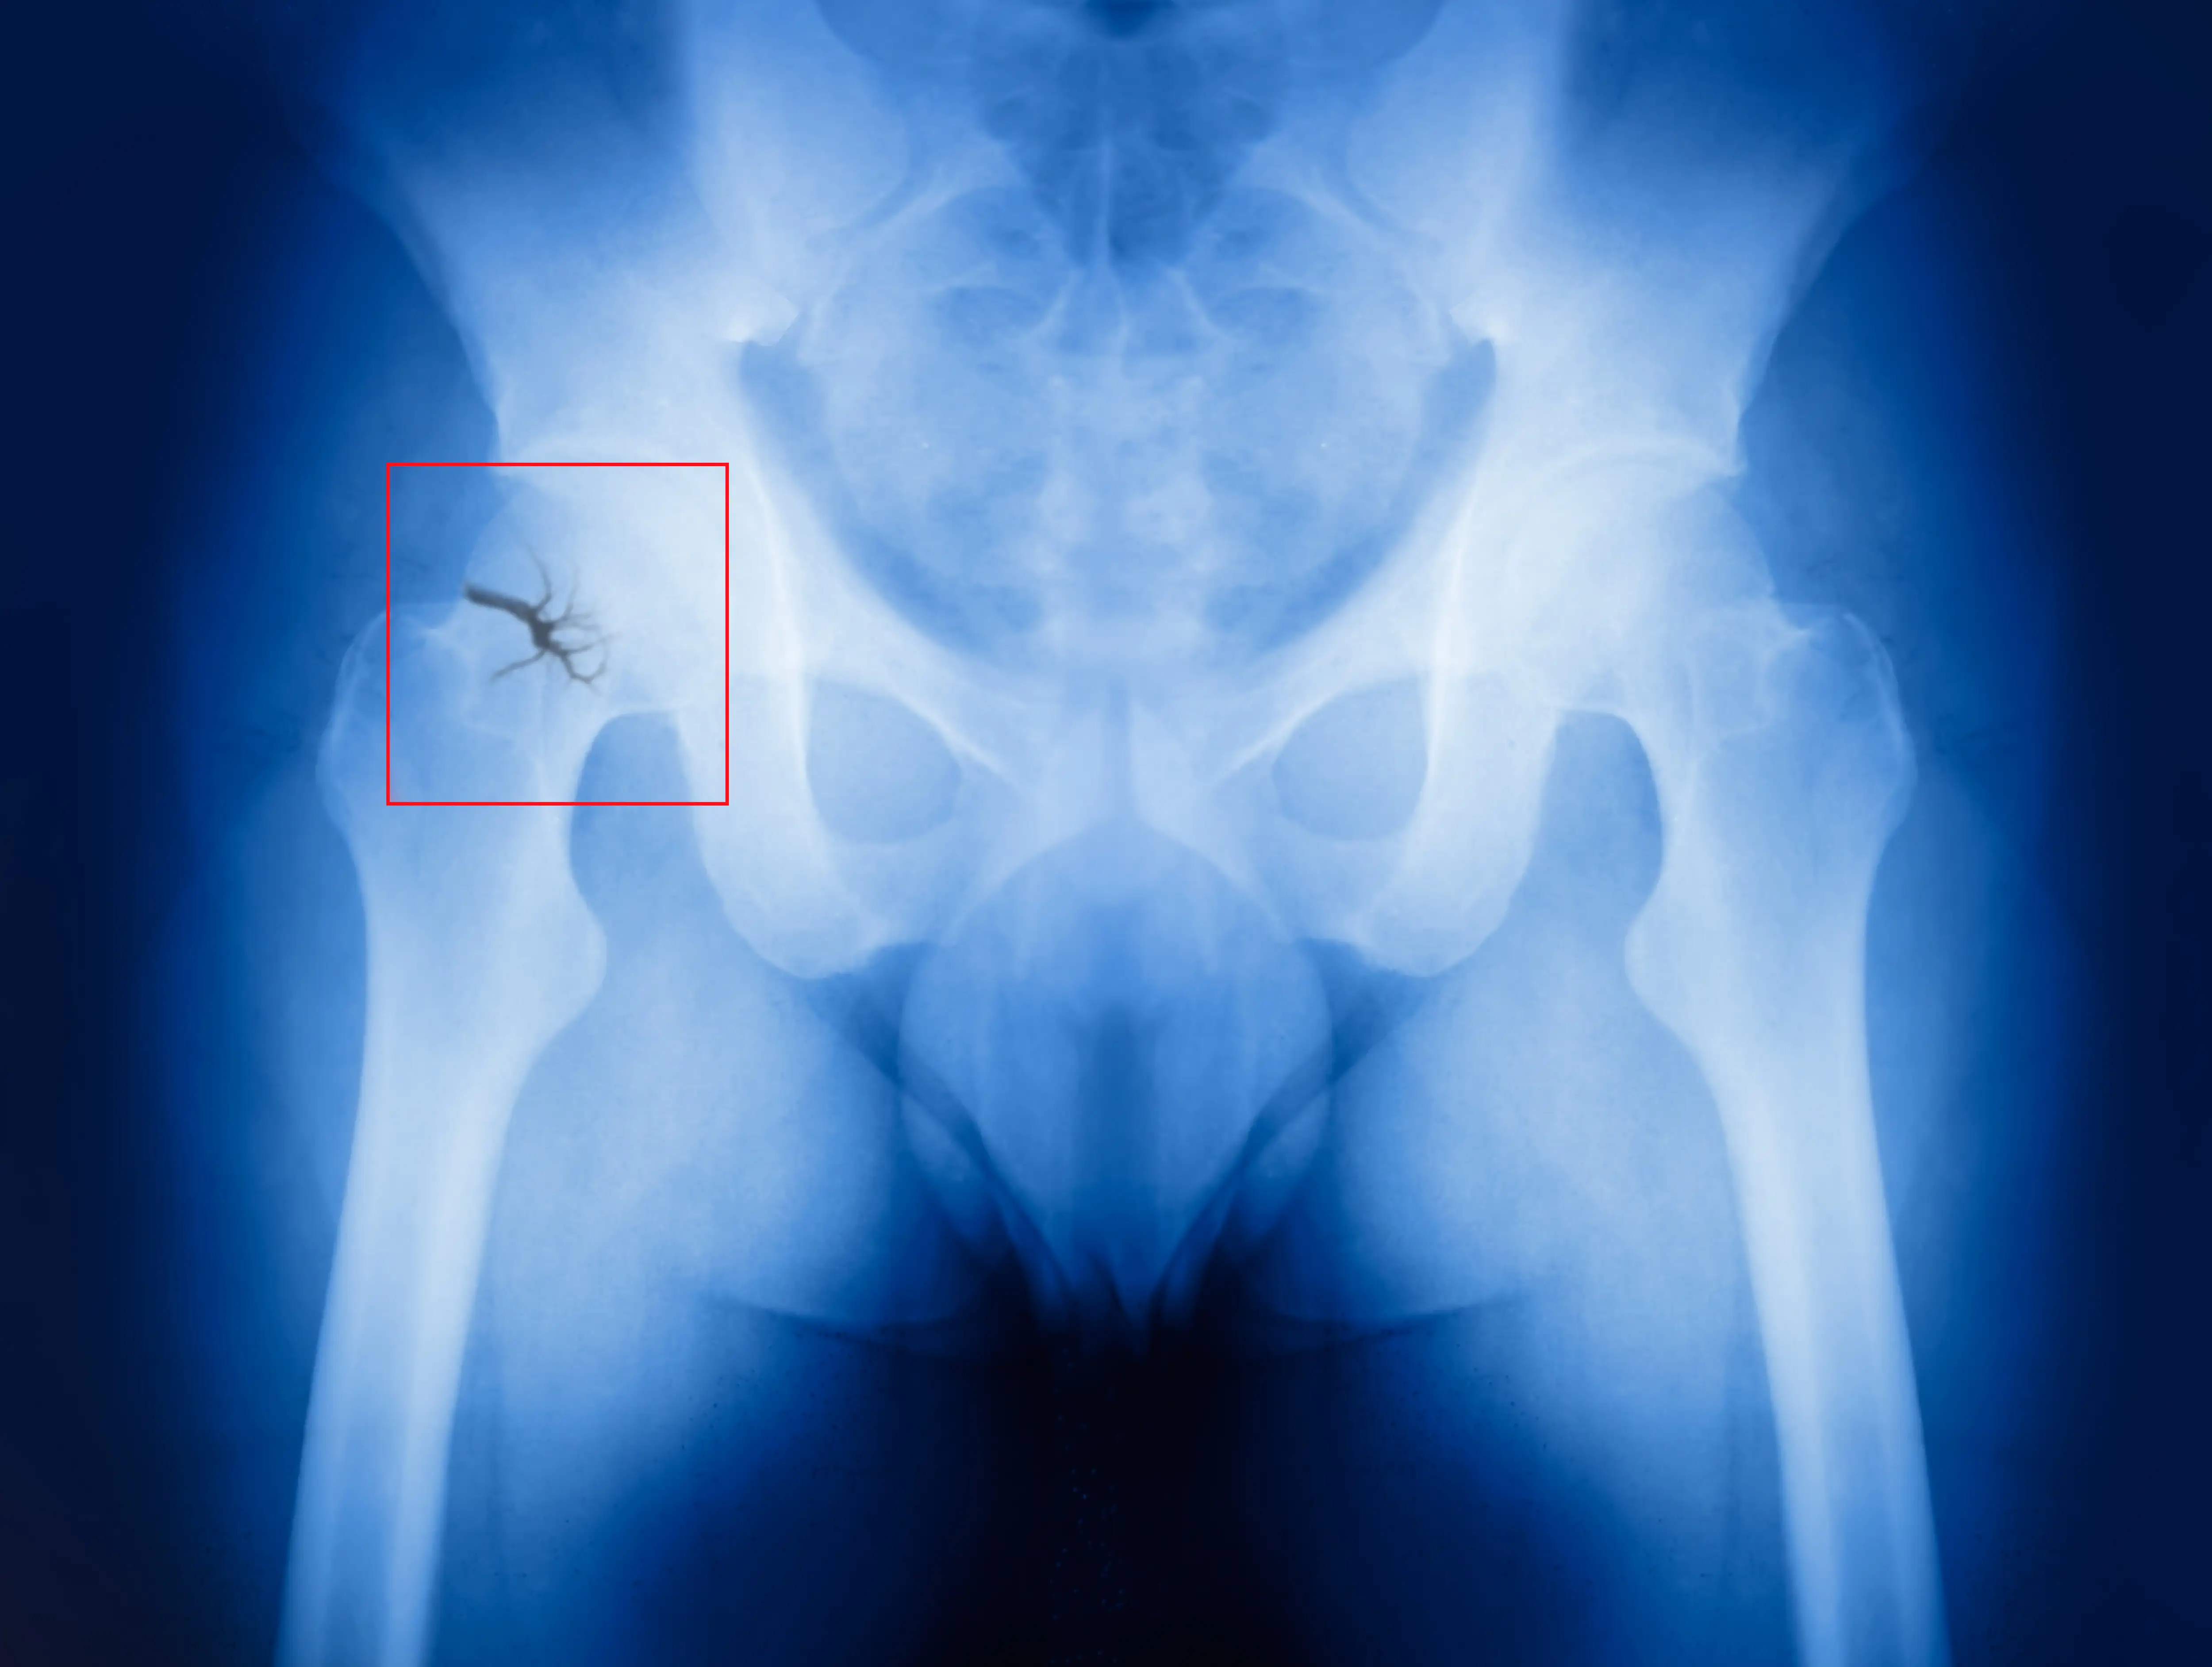

Титанові еластичні цвяхи - мінімально інвазивне рішення при переломі кісток тазу

Титанова еластична система фіксації є мінімально інвазивним хірургічним рішенням без ускладнень для відновлення стабільності таза, втраченої в результаті перелому, забезпечуючи швидке і стабільне відновлення.

Нещодавнє дослідження ефективності та безпеки титанових еластичних цвяхів (TEN) при переломах кісток тазу, результати якого були опубліковані в престижному журналі Surgical Innovation, знаменує значний зсув у парадигмі лікування. До дослідження включили 24 пацієнти, у тому числі 16 чоловіків та 8 жінок, які пройшли обстеження та лікування.

Хірургічна процедура полягала у тимчасовій фіксації переломів кісток таза за допомогою тазового фіксуючого ременя з витягом за кістку нижньої кінцівки. При специфічних травмах, таких як переломи переднього тазового півкільця та клубової кістки, застосовували закриту репозицію та інтрамедулярну фіксацію за допомогою TEN. Для забезпечення точного розміщення та вирівнювання титанових цвяхів застосовували інтраопераційну рентгеноскопію з використанням рентгенохірургічних систем типу «С-дуга» та «О-дуга».

Шляхом закритої репозиції та мінімально інвазивних розрізів переломи кісток тазу були успішно стабілізовані за допомогою еластичних титанових цвяхів. Ускладнення практично не було, у всіх пацієнтів було зареєстровано успішне загоєння ран без пошкоджень нервів або судин. Крім того, заохочувалась рання післяопераційна мобільність, що, як зазначили дослідники, дозволяло пацієнтам займатися функціональними вправами на початкових етапах відновлення.